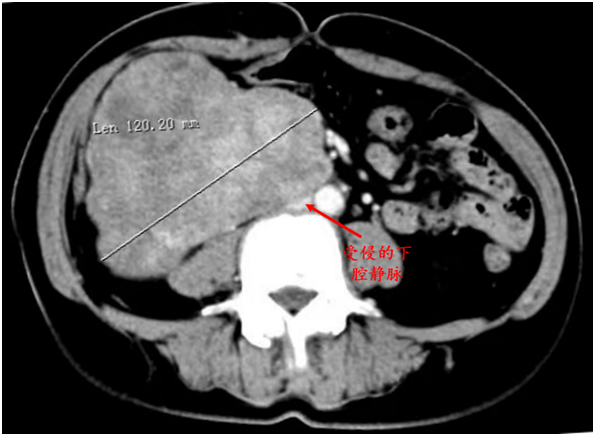

在安抚好患者的情绪后,刘海龙立刻为其进行详细的问诊和体格检查,发现患者右侧腹部有一排球大小肿物,质韧、边界不清、活动欠佳。结合患者携带的CT片子,刘海龙立刻诊断出这是位于右侧腹腔的一例巨大腹膜后肿瘤,肿瘤压迫输尿管已引起了右肾盂积水,更严重的是,肿瘤基底部与下腔静脉连接紧密,考虑存在侵犯。尽管手术难度很大,刘海龙在快速评估了肿瘤情况后,还是决定收治这位特殊患者。

由于病情复杂,刘海龙立刻组织了科内讨论,并邀请介入室、泌尿外科、手术室和麻醉科等共同为患者制定手术方案。经过周密的手术计划和充分准备,决定先由介入室的汤旻副主任医师和蔺松若主治医师行选择性肿瘤供血动脉栓塞术,再行肿瘤切除。手术由普外科林谋斌主任医师和刘海龙副主任医师联手开展,术中探查发现腹膜后肿瘤与右半结肠、十二指肠水平部、右肾、右肾静脉、右输尿管粘连紧密,其基底部与下腔静脉更是关系密切、不能剥离。

但凭借深厚的手术经验,两位医生沉着应战、精细操作,逐步分离肿瘤与周围粘连紧密的组织,并成功切除受侵的部分下腔静脉,予以严密的缝扎止血。历经3小时的攻坚克难,这台高难度手术顺利结束,完整切除了这颗约15×12×9cm大小的巨大肿瘤,完好保留了十二指肠、右肾及输尿管、右半结肠等周围脏器,并且术中出血仅百余毫升。